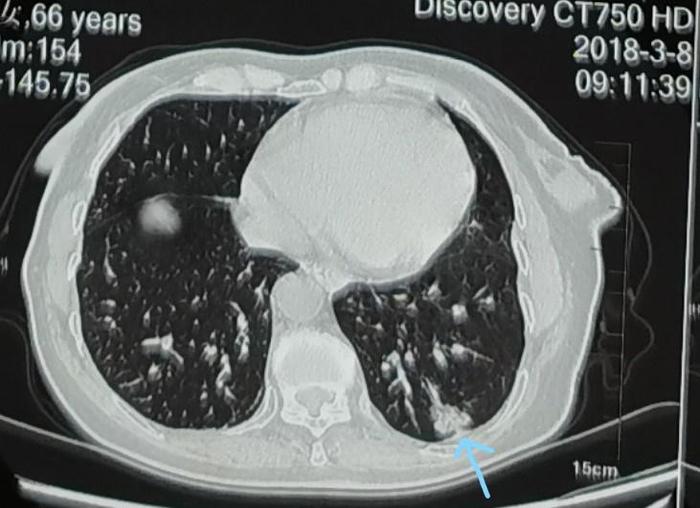

上图可见蓝色箭头指示的2018年3月左下肺混合磨玻璃结节,大小约20毫米,实性成分为主,照片上结节内部有一些发暗的的小缝隙,使这个混合磨玻璃结节看起来像一个洋葱头。这是一个混合磨玻璃结节,但是当时接诊的医生由于水平有限,认为是慢性炎症,没有认出这个结节其实是一个实性成分为主的混合磨玻璃结节。

上图可见蓝色箭头指示的2019年7月左下肺混合磨玻璃结节,可见仍然为20毫米,变化不大。